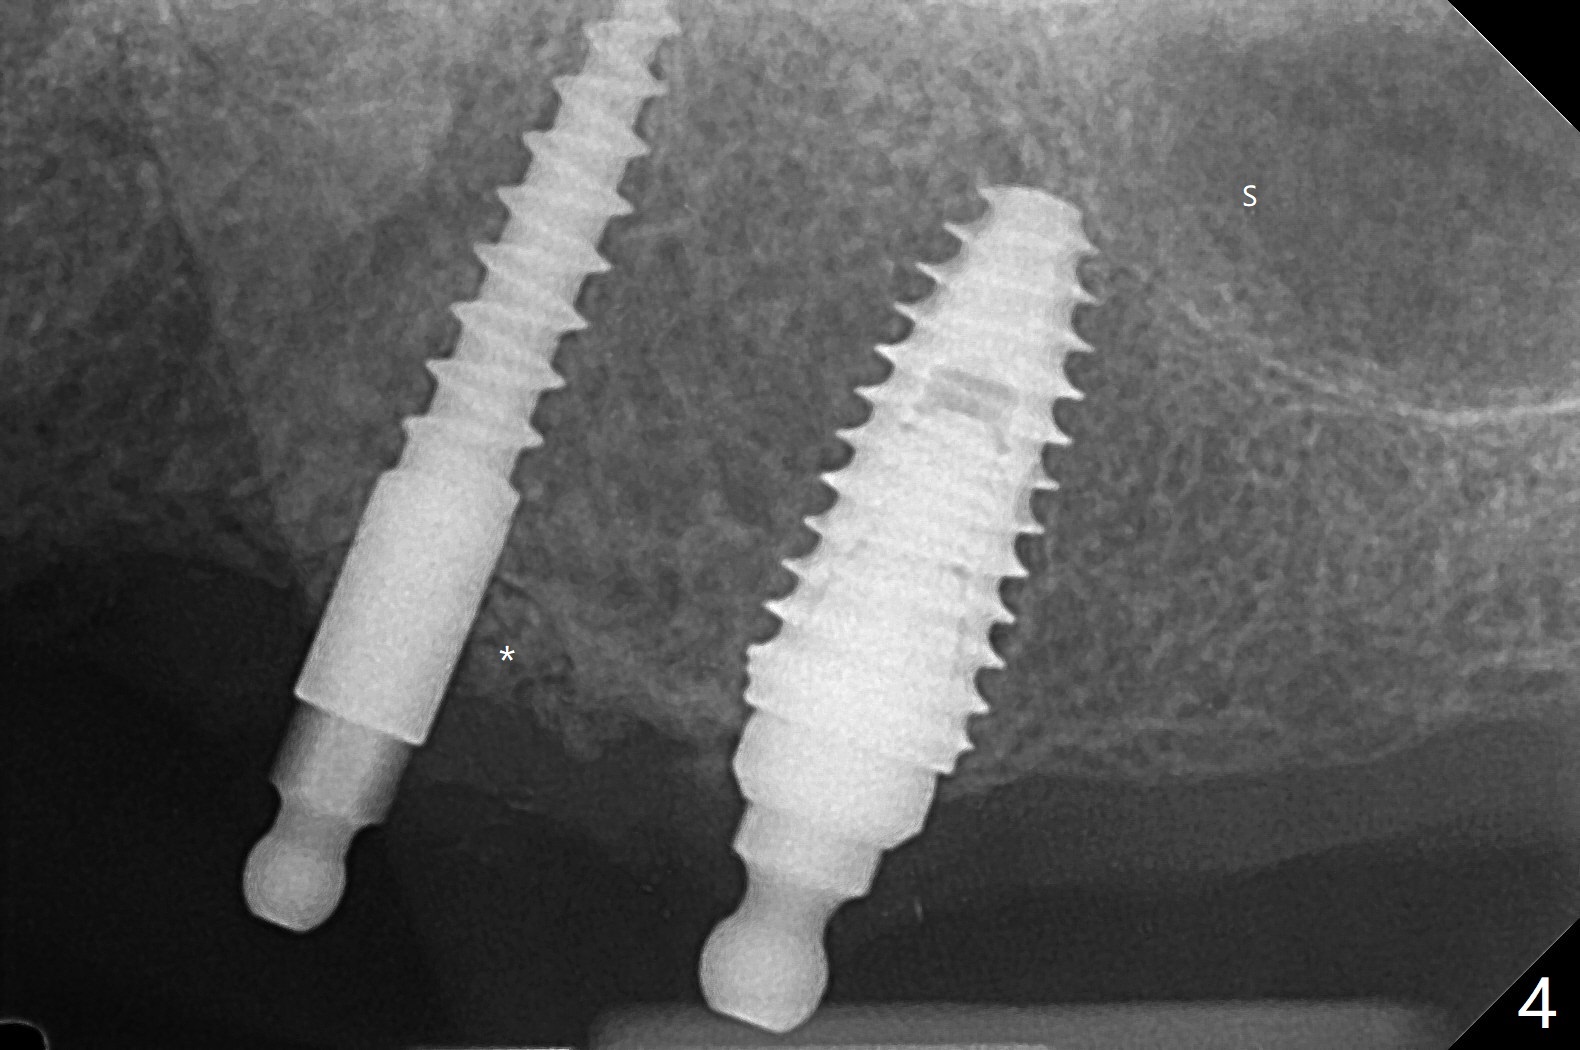

63岁女有上下活动局部假牙,由于右下侧切牙折裂(26号牙)就诊,保守处理(重新粘固)。虽然病人满意上颌义齿,而且非常害怕牙科治疗,并不想多花钱,但是对左上两个植牙固位假牙有兴趣。原计划在尖牙和第二双尖牙(11和13号牙),CT检查表明11号牙处牙槽骨太窄,所以改为12和13处种植(3.5乘10,4乘10毫米)。12号牙处牙槽嵴截除后,颊舌侧宽度仍不够,钻洞直径2毫米(图一),似乎不得不用一体式带球帽植体(1-piece implant with ball abutment),2.5乘10(4)毫米(图二至四;N: 鼻腔,S: 上颌窦),并且在它周围植骨(图三,四 *)。在假牙相对位置创造空间后,做软衬里(图五)。对于恐惧病人,尽管带球帽植体精确度要求不高,导板还是必要的。一周以后病人十分感激,因为没有痛(图六)。术后一个月她很高兴告诉我们自从植牙后,托牙下面不容易积累食物了。